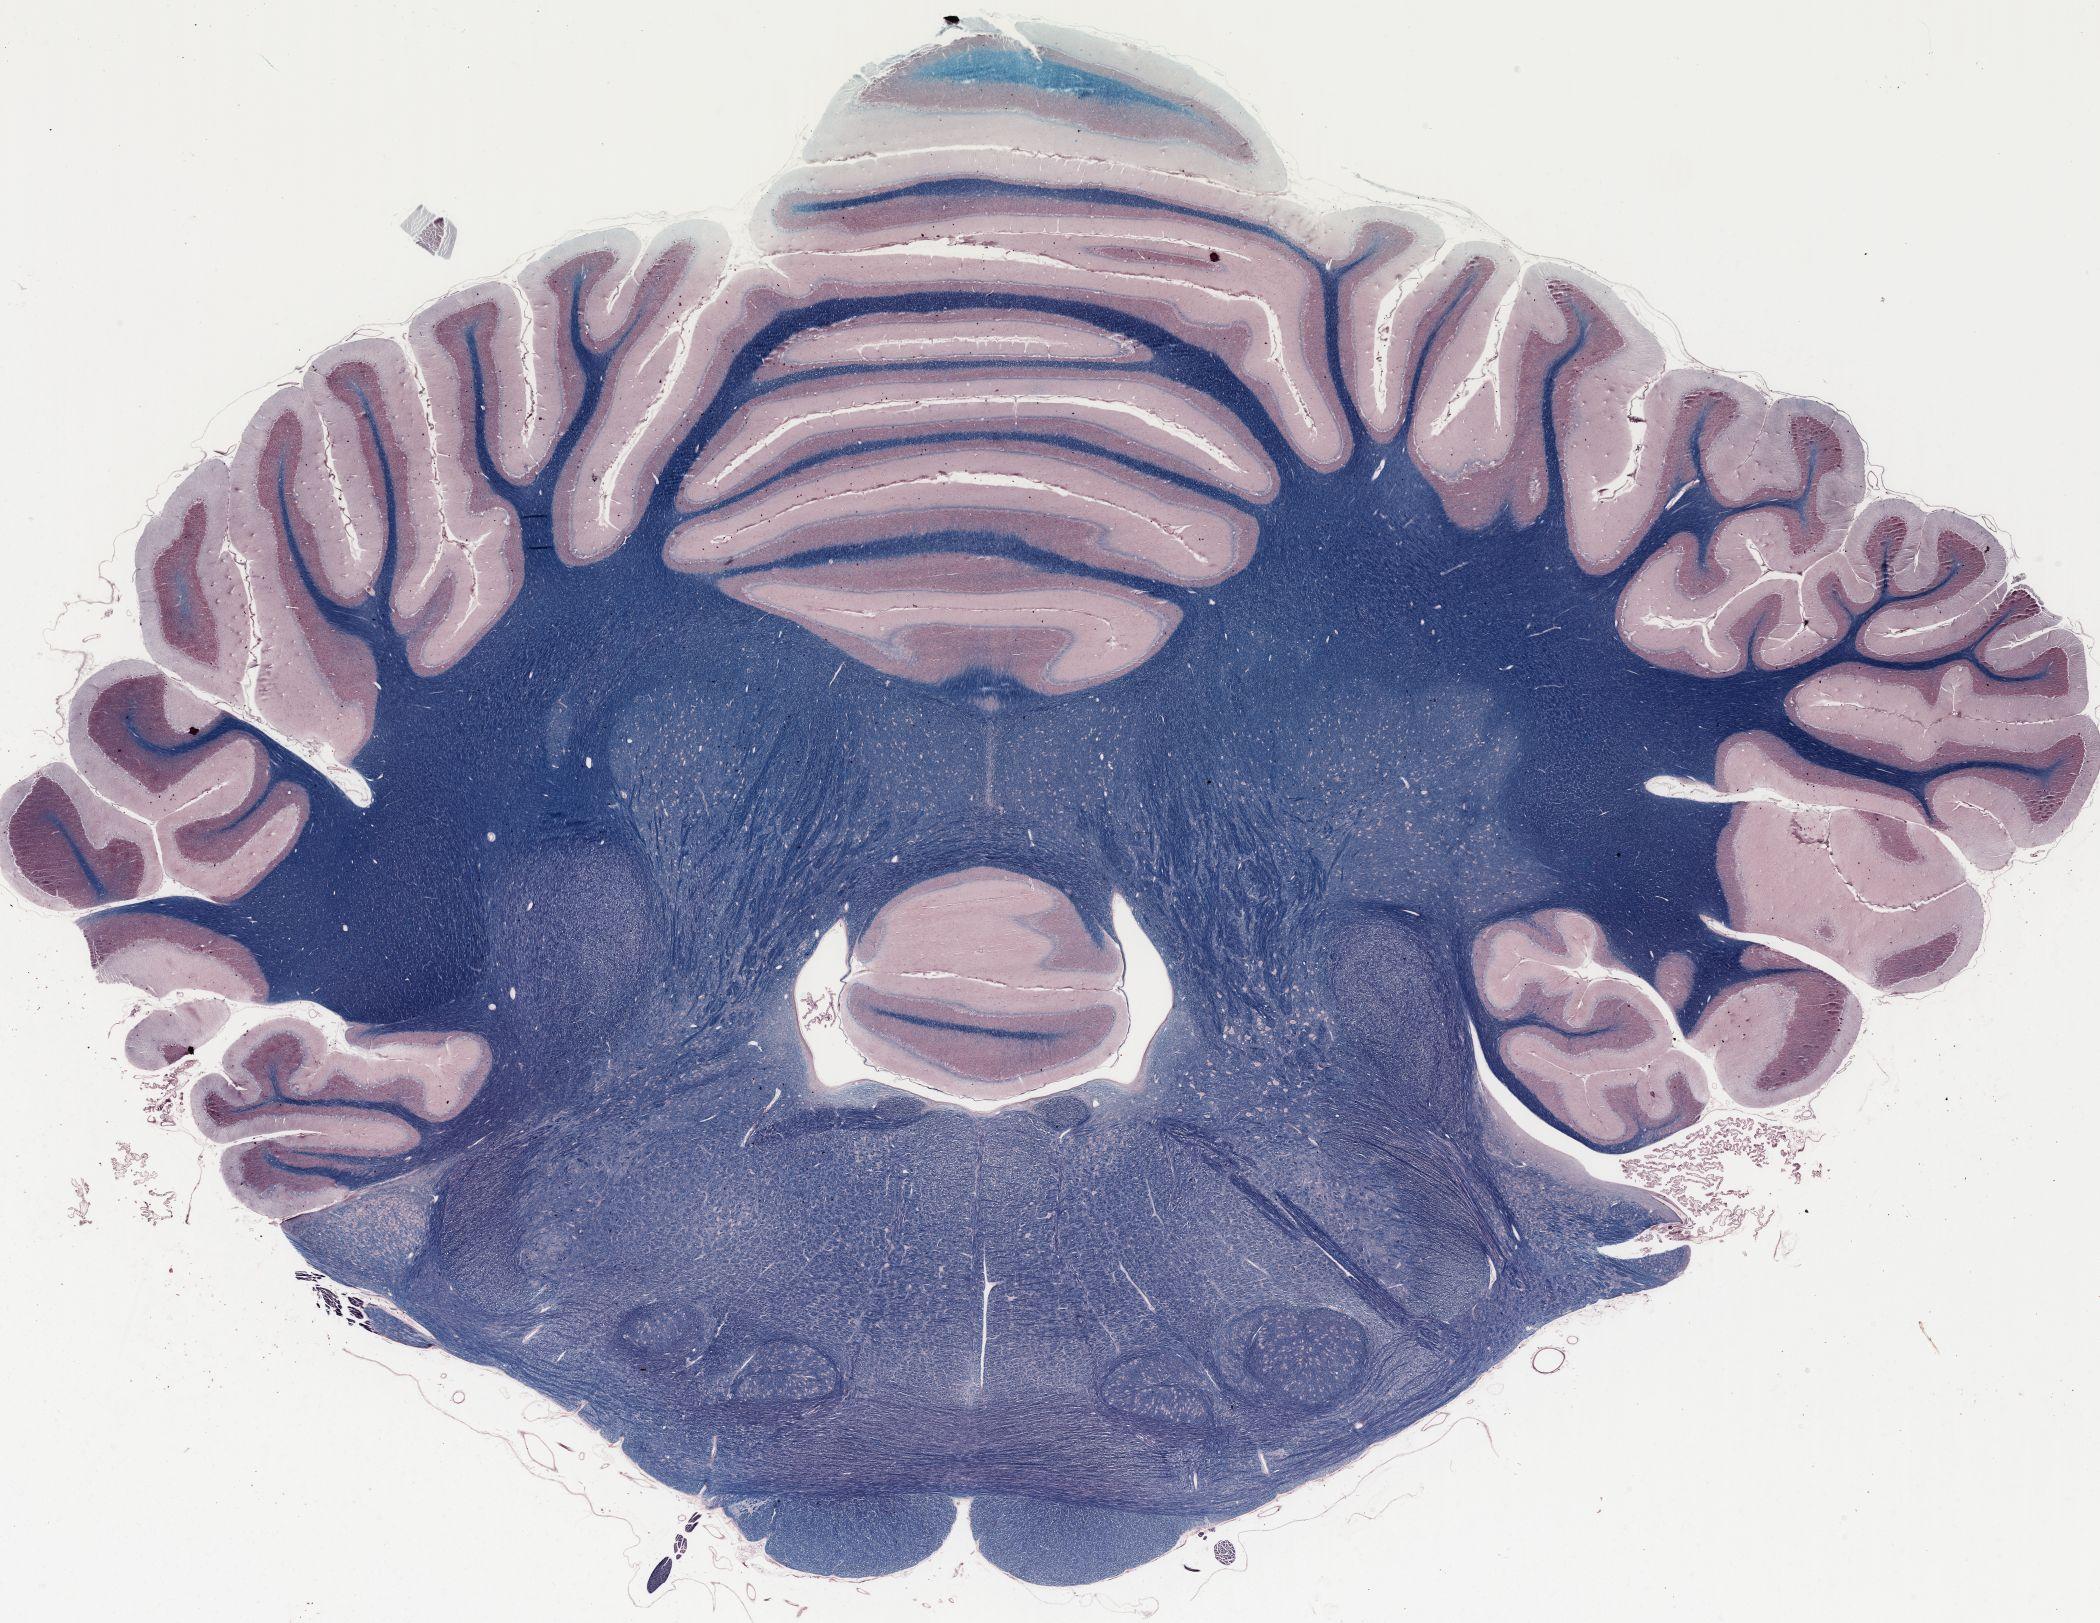

Datasets -> Canis Lupus -> Luxol Fast Blue, coronal, histo, Whole-Brain, adult

[ Metadata ]   ·   Source: Thomas Fletcher